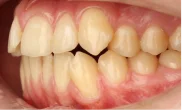

Обратилась с жалобой на скученность верхней и нижней челюсти средней степени тяжести — рецидив после подросткового лечения (ретейнер не носила).

Ход лечения

общий срок — 18 месяцев, 11 визитов для замены дуг и контроля. На 4-м месяце — видимое улучшение выравнивания. На 12-м — начат этап коррекции прикуса

с межчелюстными эластиками. На 18-м — снятие, установка ретейнеров.